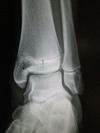

Grey Turner’s sign

Flank ecchymosis

Acute pancreatitis